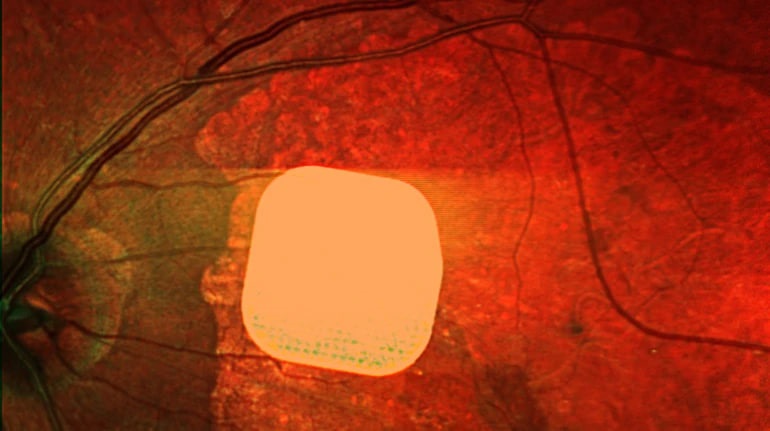

Вчені створили кібер-око для людей із вадами зору

Міжнародні дослідники створили новий очний імплантат, який може частково відновити центральний зір у людей, які втратили його через важку форму…

Британські лікарі частково повернули зір пацієнтам за допомогою мікрочипа

Британські лікарі успішно випробували новий електронний імплант Prima, який допомагає частково відновити зір у пацієнтів із макулодистрофією. Цей мікрочип встановлюють…